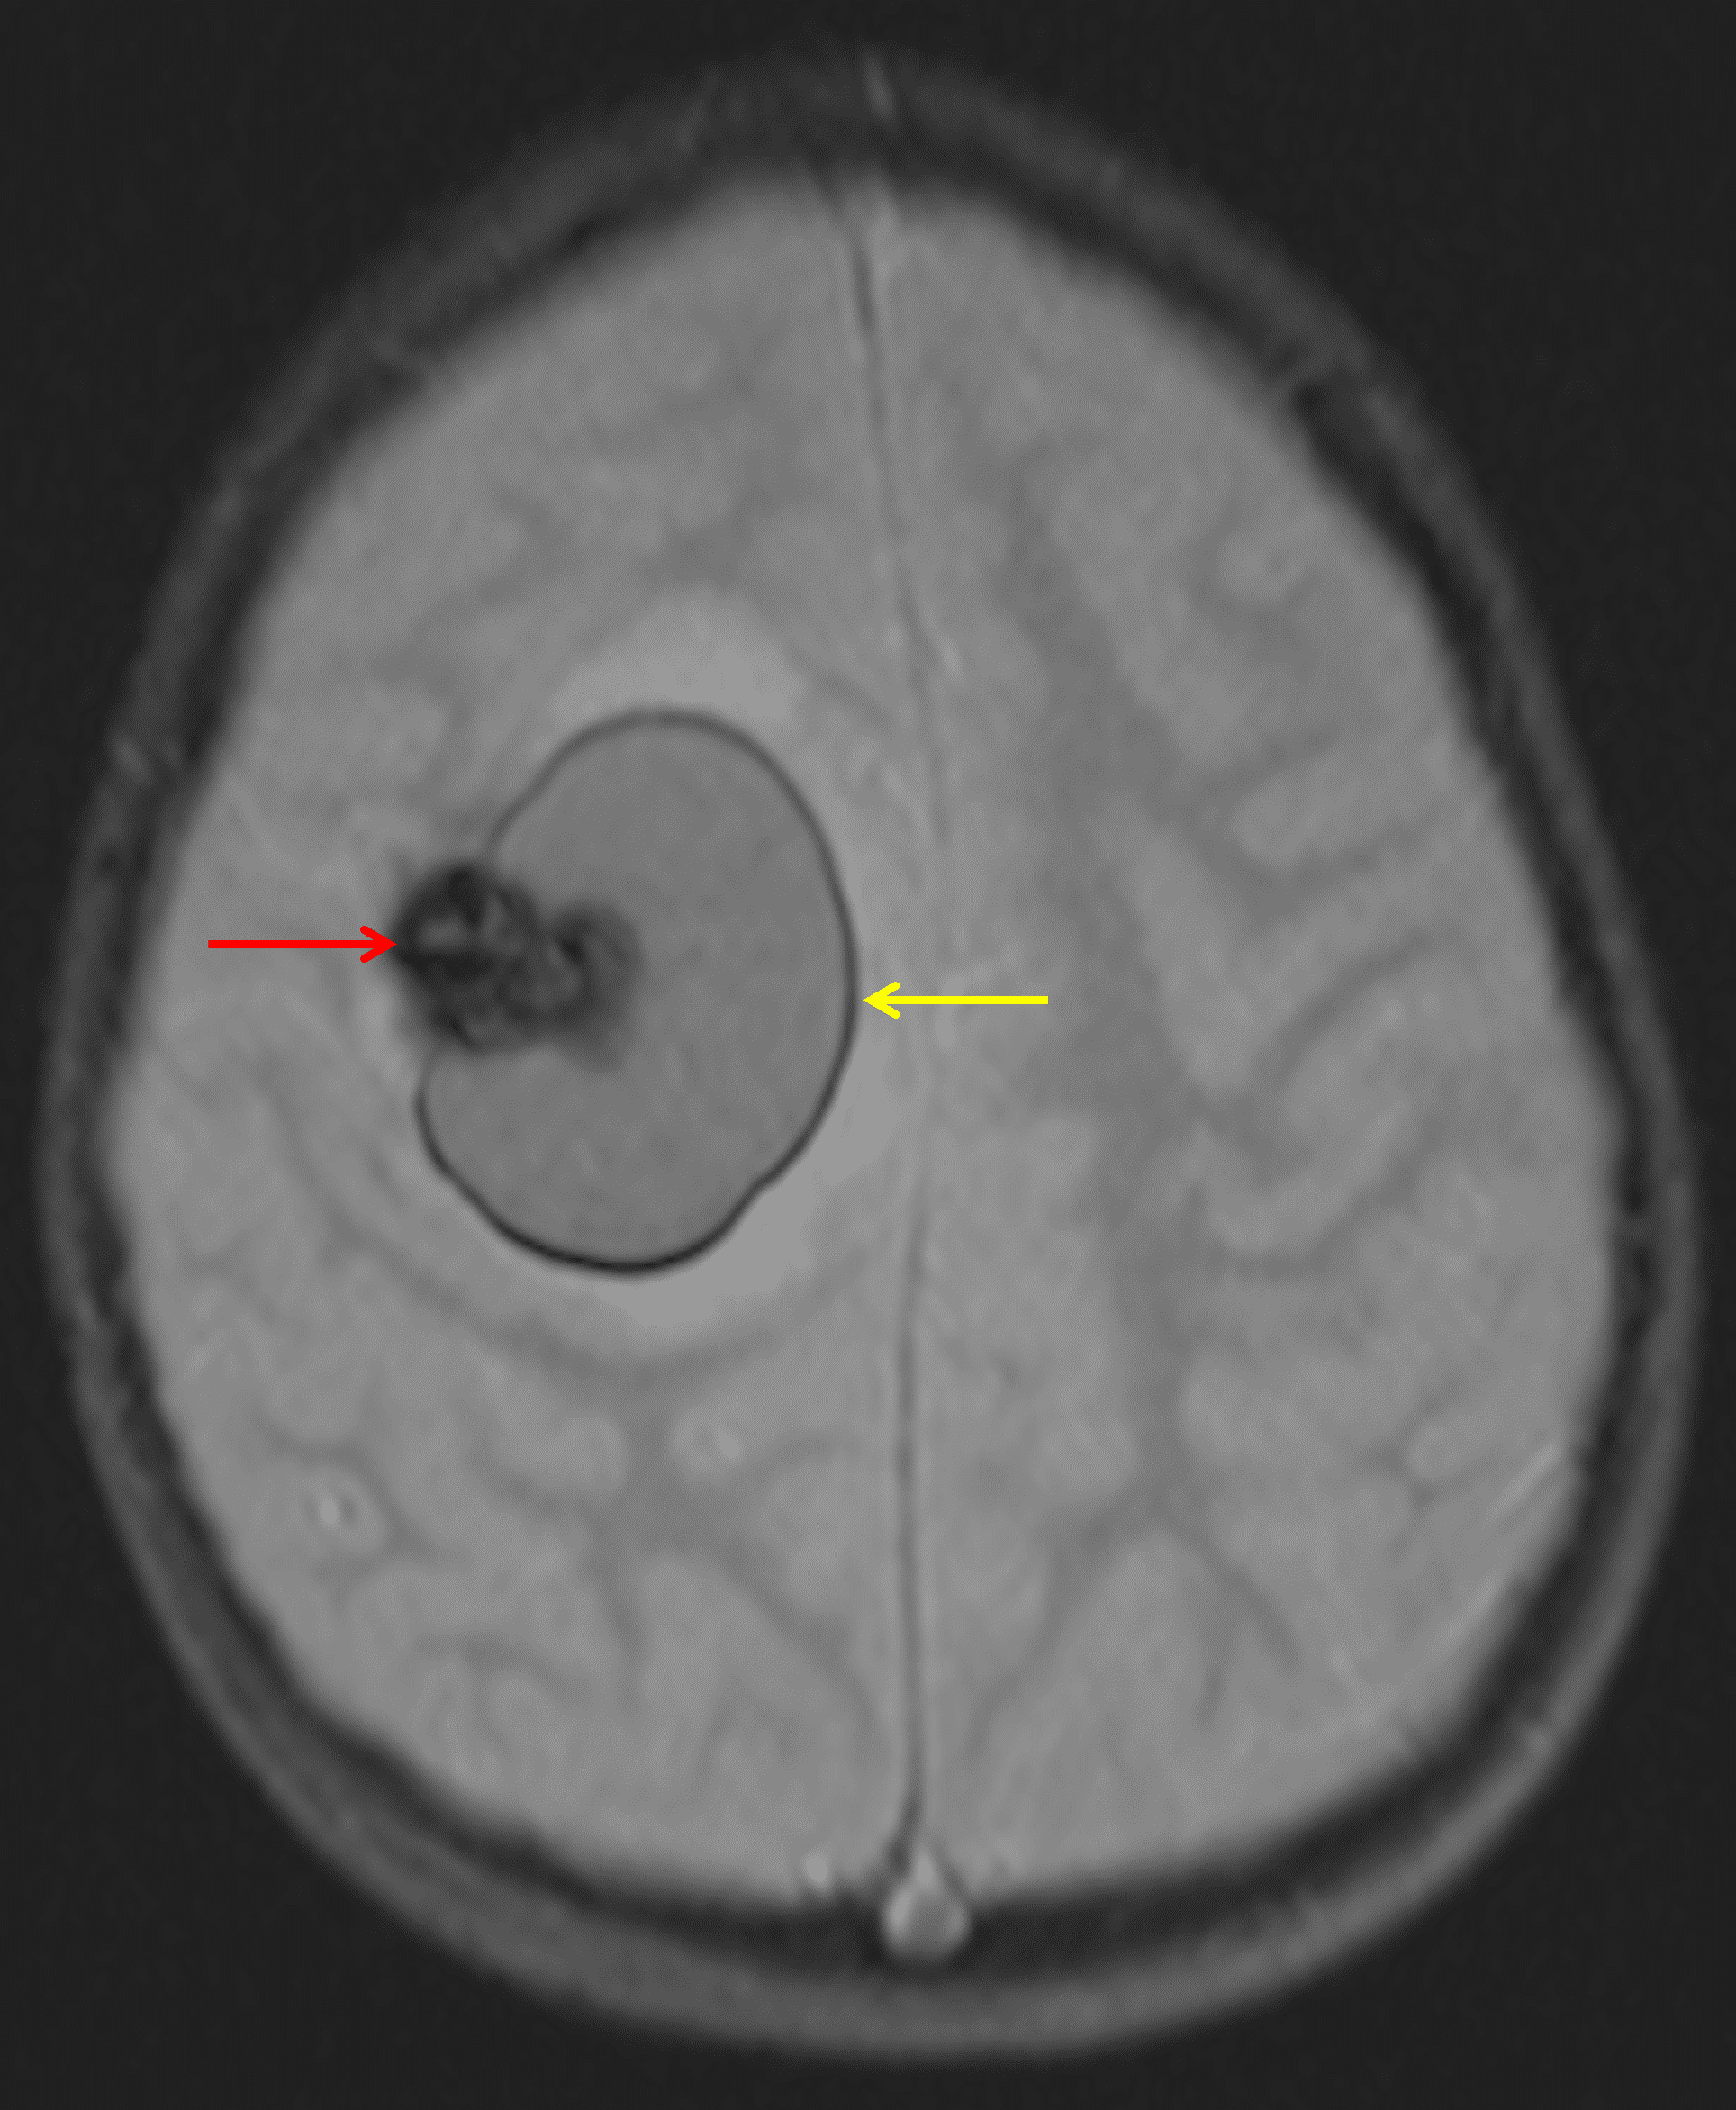

The lesion demonstrates extensive corresponding susceptibility artifact (red arrow). In addition, there is a rim of susceptibility artifact along the adjacent hematoma (yellow arrow).